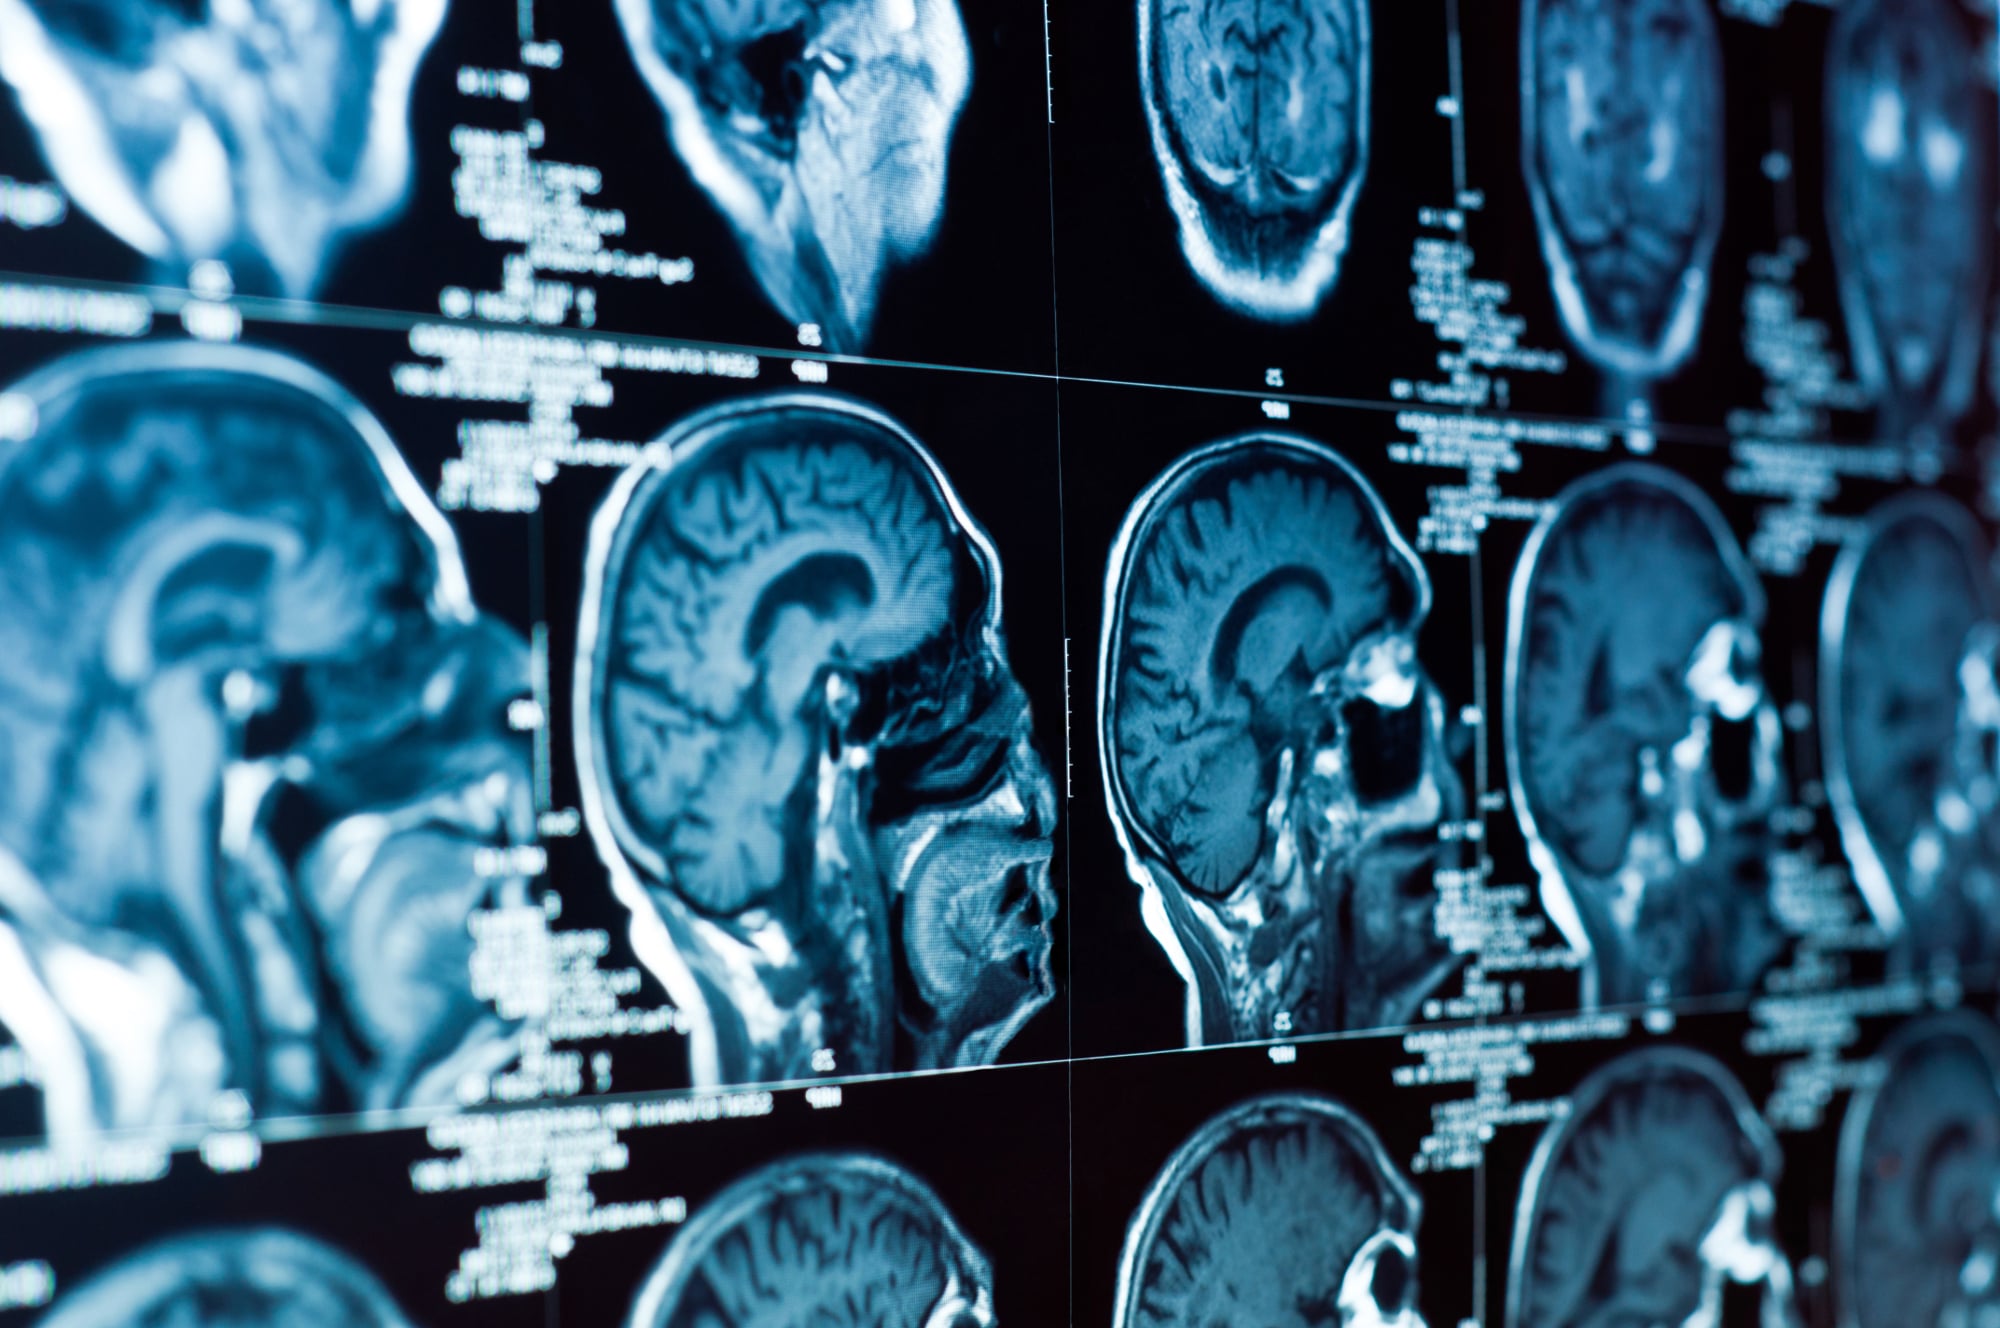

МРТ головного мозга: показания и результаты

Раздел: Визуальный дайджест